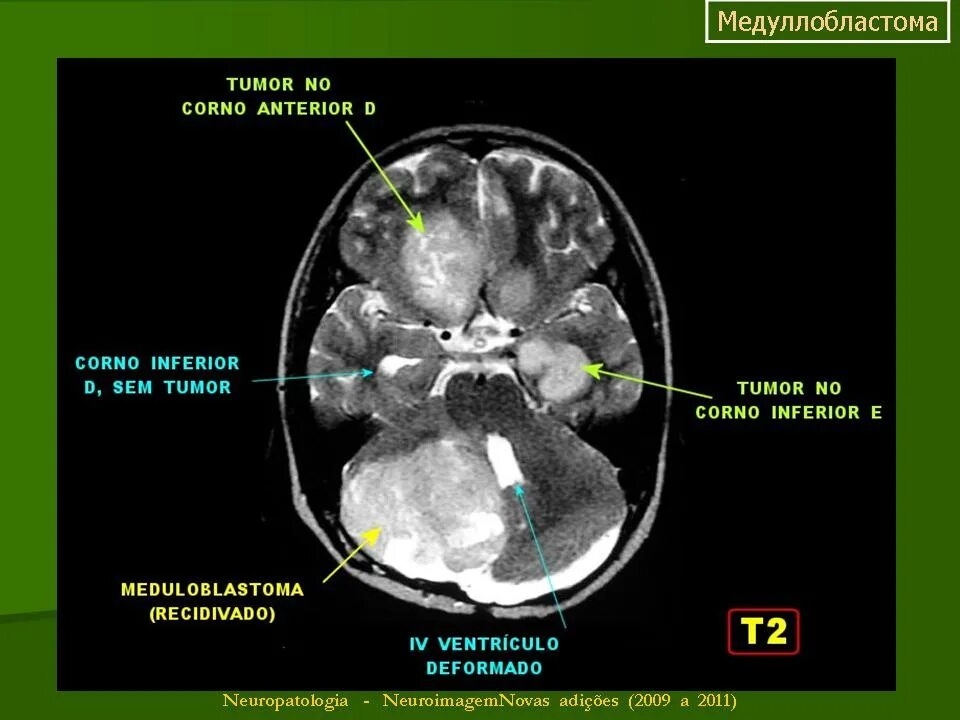

Медуллобластома это